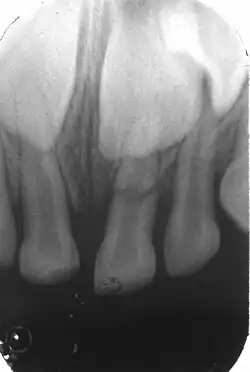

Kronenfraktur 21; die rosa durchschimmernde Pulpa ist gut zu sehen; eventuell mit einer kleinen punktförmigen Pulpaeröffnung

Bei den Zahnfrakturen unterscheidet man je nach Lokalisation zwischen Kronenfraktur (an der klinischen Krone des Zahnes) und Wurzelfraktur (an der Zahnwurzel). Nach dem Verlauf der Frakturlinien wird zwischen Quer-, Längs- und Schrägfraktur unterschieden.

Kronenfraktur

• Dentin-Frakturen (im Zahnbein) – genauer: Schmelz-Dentin-Fraktur, da eine Dentinfraktur nur bei gleichzeitiger Fraktur des Zahnschmelzes vorliegen kann – mit oder ohne Pulpenbeteiligung

• Dentin-Frakturen mit Eröffnung der Zahnpulpa